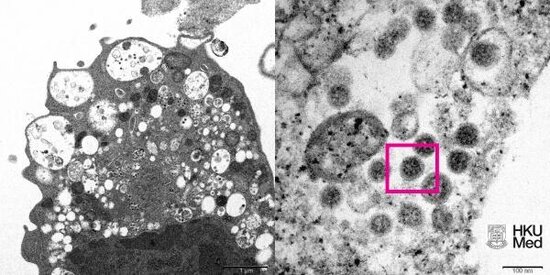

Honkonq Universitetinin tibb fakultəsinin alimləri COVİD-19 koronavirusunun omikron-ştamının dünyada ilk dəfə olaraq təfərrüatlı görüntüsünü əldə ediblər.

Milli.Az CNN-ə istinadən bildirir ki, mikroskop altında çəkilmiş elektron mikrofotoda SARS-CoV-2 Omicron ştamına yoluxmuş meymunun böyrək hüceyrəsi əks olunub.

Kadrda kiçik qara virus hissəciklərin olduğu vezikulları böyüyən xəsarətli hüceyrə aydın görünür.

Fotonun sağında isə üzərində koronavirus "tikan"ları olan virus hissəcikləri var.